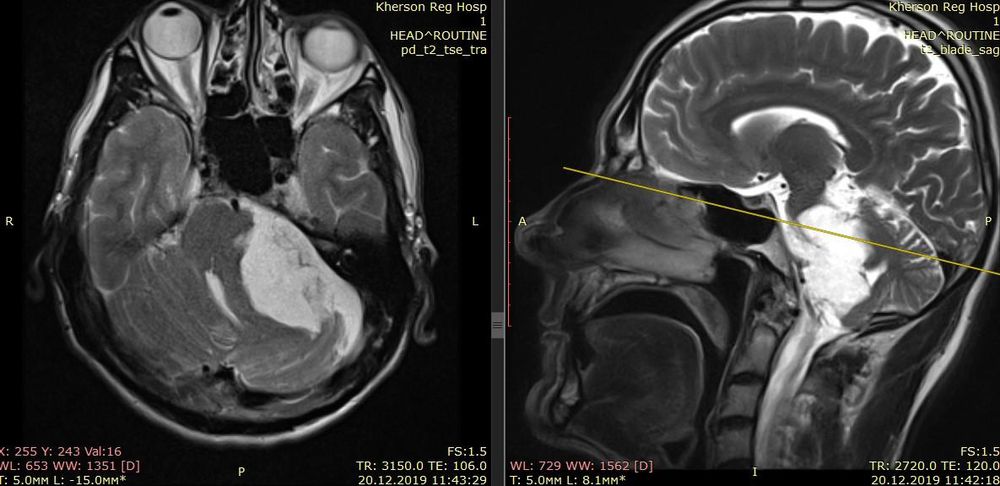

Вилучення пухлин шлуночкової системи головного мозку являє значні труднощі. У випадках, коли це не може бути виконано в повному обсязі, виконується так звана шунтуюча операція для відведення надлишку спинномозкової рідини (ліквору) з головного мозку в черевну порожнину з використанням спеціальної трубчасто-клапанної системи, яка знижує внутрішньочерепний тиск та покращує стан пацієнта.

Видалення метастатичних церебральних пухлин (операція) можливо, якщо вони являються одинокими та розташовані в доступній для вилучення зоні.

У деяких випадках, коли навіть часткове видалення пухлини головного мозку не представляється можливим, обсяг операції зводиться до декомпресійної трепанації черепа з метою зниження внутрішньочерепного тиску і хоча б тимчасового поліпшення стану пацієнта.